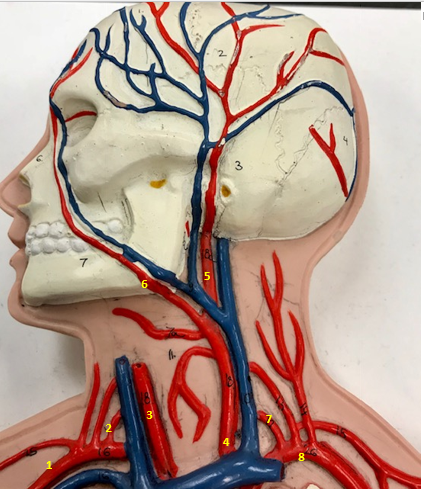

Right subclavian artery

Name #1

Supplies blood to right arm and shoulder

Function of right subclavian artery (1)

Right vertebral artery

Name #2

Supplies blood to brain and spinal cord

Function of right vertebral artery (2)

Right common carotid artery

Name #3

Supplies blood to right neck and head

Function of right common carotid artery (3)

Left common carotid artery

Name #4

Supplies blood to left neck and head

Function of left common carotid artery (4)

Left external carotid artery

Name #5

Supplies blood to face neck and skull

Function left external carotid artery (5)

Left facial artery

Name #6

Supplies blood to face and neck

Function of left facial artery (6)

Left vertebral artery

Name #7

Supplies blood to brain and spinal cord

Function of left vertebral artery (7)

Left subclavian artery

Name #8

Supplies blood to left arm and shoulder

Function of left subclavian artery (8)